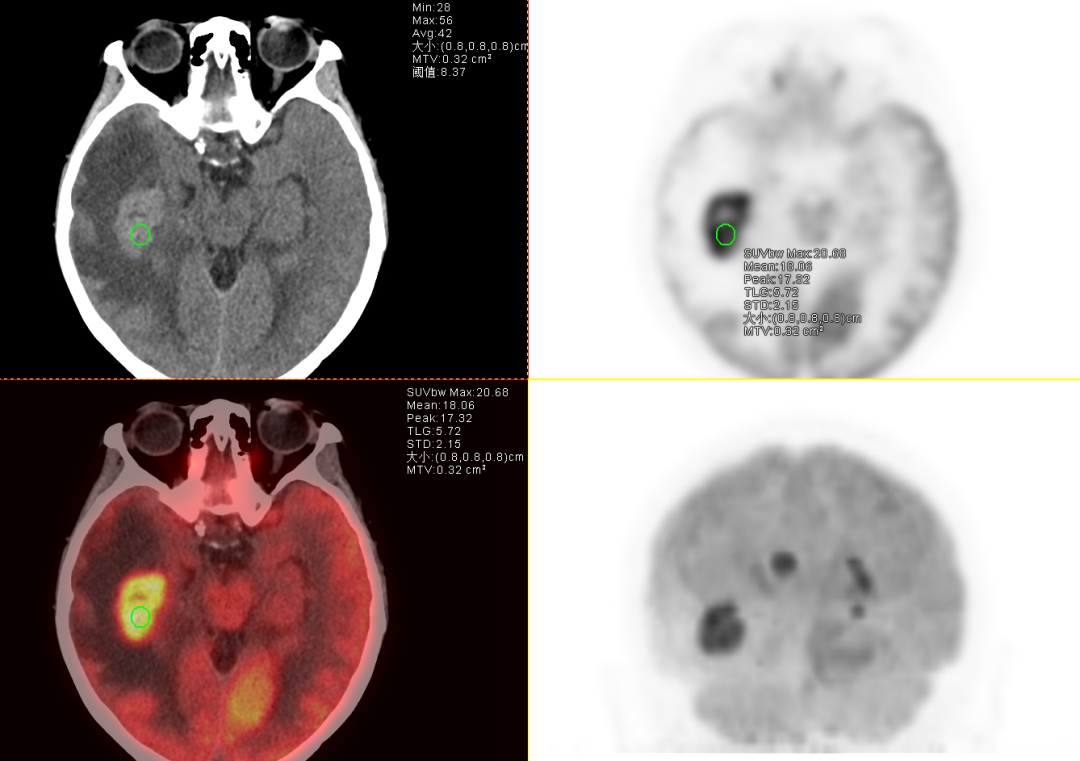

为明确原发灶及病变性质,王女士来到贵州医科大学附属肿瘤医院进行了全身PET-CT检查,结果呈现几点特征:颅内多发结节代谢显著增高,较大的结节位于右侧颞叶,大小约3.2*2.1cm,且病灶周围水肿区的代谢相对较低,这很符合中枢神经系统淋巴瘤的表现。全身其他部位未见明确高代谢肿瘤灶,包括常见转移部位如肺、肝、骨等,因此基本排除实体瘤转移的可能。中枢神经系统淋巴瘤虽影像上常表现为“多发占位+水肿”,但其代谢活性通常更均匀且显著(因淋巴瘤细胞增殖活跃,葡萄糖代谢极高),而转移瘤水肿区代谢增高(因炎性反应),且多能找到原发肿瘤,因此,结合PET-CT全身无原发灶的证据,最终诊断为“原发性中枢神经系统淋巴瘤”。

患者PET-CT检查